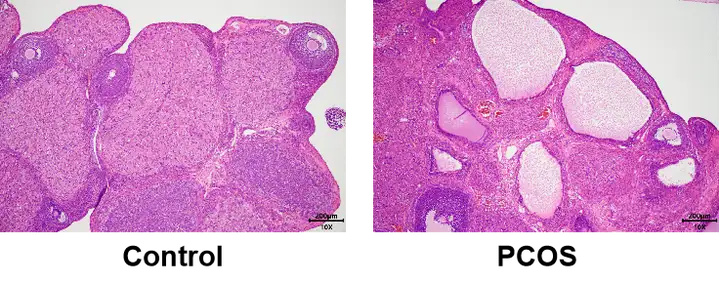

模型验证:正常组大鼠卵巢组织中,可见不同发育时期的卵泡和少量黄体,颗粒细胞排列整齐;模型组中,可见显著囊状扩张卵泡,颗粒细胞层数减少,未成熟的小卵泡数量明显增加,卵母细胞消失,表明模型成功。

图3 HE模型验证(100X)